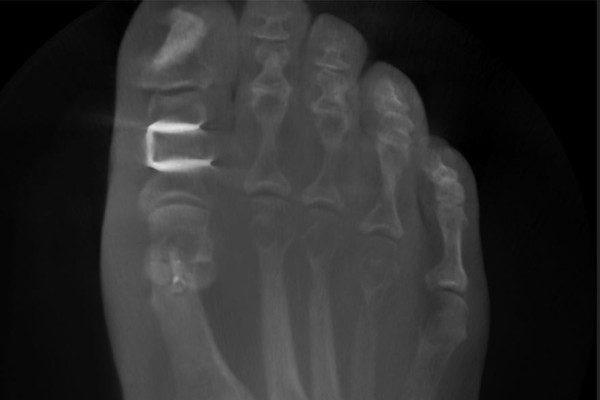

Über einen kleinen Hautschnitt auf der Innenseite des Grundglieds der Großzehe wird ein keilförmiges Knochenstück entnommen. Der Knochen wird dann in die korrigierte Stellung gebracht und mit einer Titan-Klammer (Staple) stabil fixiert. Die Klammer verbleibt dauerhaft im Körper – eine Entfernung ist in der Regel nicht notwendig.

Wir bevorzugen in den meisten Fällen die mini-open Technik. Sie ermöglicht eine direkte Sicht auf den Knochen und damit eine präzise Dosierung der Korrektur – das heißt, wir können genau bestimmen, wie viel Knochengewebe entnommen wird. Das ist entscheidend für das Ergebnis. Eine retrospektive Vergleichsstudie mit 210 Füßen zeigte, dass bei der minimalinvasiven Variante in über 50 Prozent der Fälle die laterale Gegenkortikalis versehentlich perforiert wurde – bei der offenen Technik waren es nur 14 Prozent. Zudem war die knöcherne Konsolidierung bei der offenen Methode nach 6 Wochen abgeschlossen, bei der minimalinvasiven erst nach 12 Wochen (Schilde S. et al., Foot Ankle Int, 2021).

Welches Implantat wird bei der Akin Osteotomie verwendet?

In der Regel verwenden wir eine Titan-Klammer (Staple), die den korrigierten Knochen stabil fixiert. Bei der minimalinvasiven Variante kommt stattdessen eine Schraube zum Einsatz. Welches Implantat sinnvoll ist, hängt von der gewählten Operationstechnik ab.